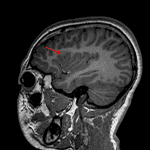

Age: 10

Sex: Female

Indication: Epilepsy

- Area of nonmasslike T2/FLAIR signal hyperintensity involving the cortex and juxtacortical white matter of the right inferior frontal gyrus and more subtle T2/FLAIR hyperintense signal radiating deep toward the ventricular margin

- Associated blurring of the gray-white interface

- No corresponding enhancement or restricted diffusion

Focal cortical dysplasia (FCD)